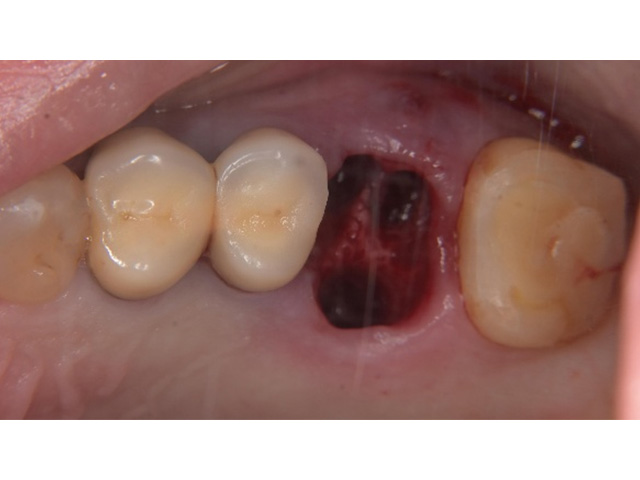

Before

親知らず移植後当日

After(移植後2か月)

After(移植後2か月)2

| 主訴 | 左下の奥歯がズキズキ痛む |

|---|---|

| 治療内容 | 左下第一大臼歯抜歯し左下智歯(親知らず)移植後の根管治療 |

| 治療回数・期間 | 7回(3か月)※根管治療は2回 |

| 費用 | 保険適応 |

| リスク・副作用 | 根管治療は術前の精密な診査診断および無菌環境下での治療によって成功率は高まってきましたが治療の成否を決める多くの要素があるため、根管治療がなされた後も再治療や外科処置、抜歯となる可能性が少なからずあります。また治療中には器具の破折や穿孔、修復物の損傷、歯の破折、術中・術後の痛みや腫れが生じることが稀にあります。根尖病変(再感染)を防ぐには適合の良好な補綴物を作製することや定期的なかみ合わせのチェックが必要です。 |